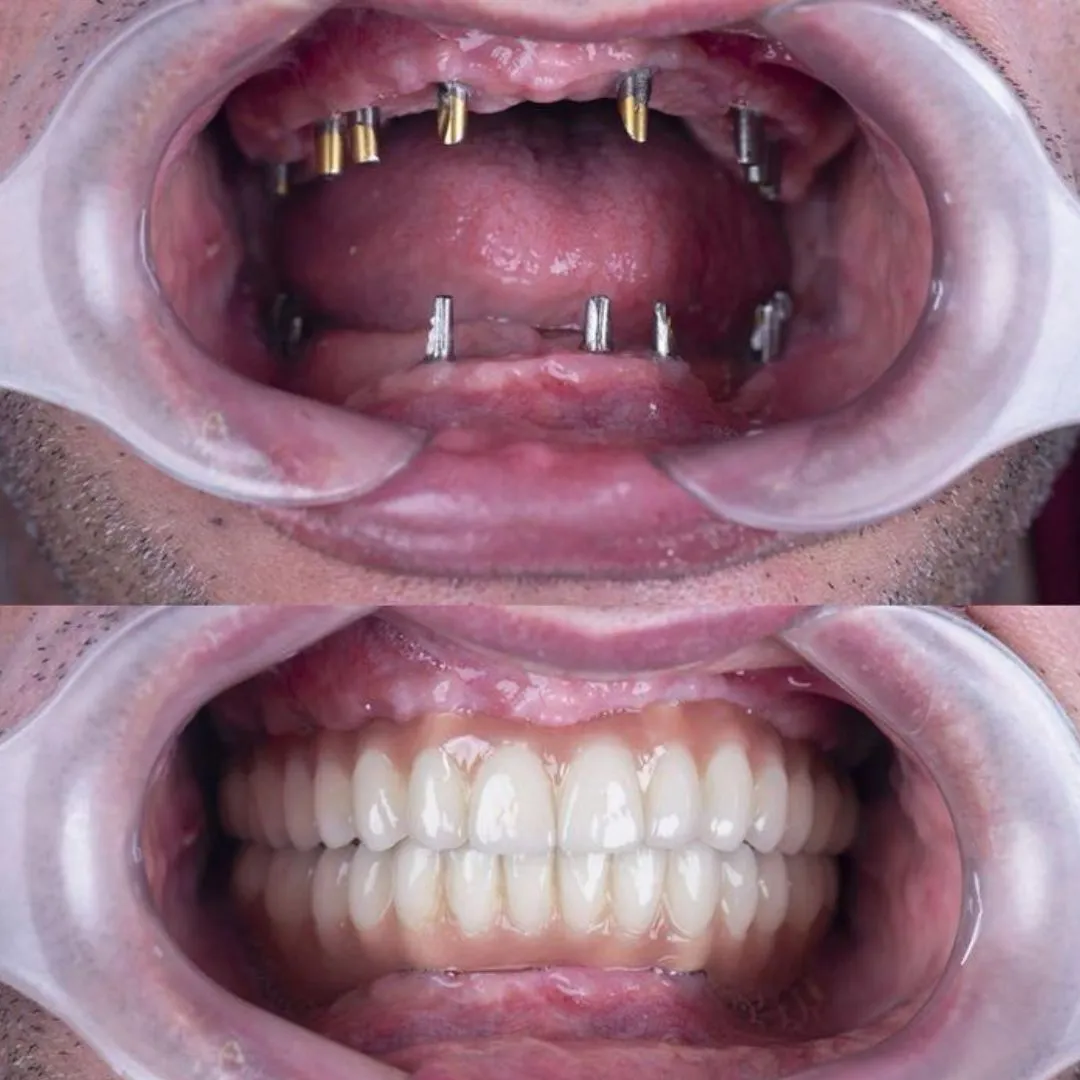

I had my dental implants done at the clinic. The process was done very well and the implants are performing exceeding well. The team is meticulous and delivers superlative performance .

Dental Implants Advanced, long-lasting solutions to replace missing teeth with precision and aesthetics.